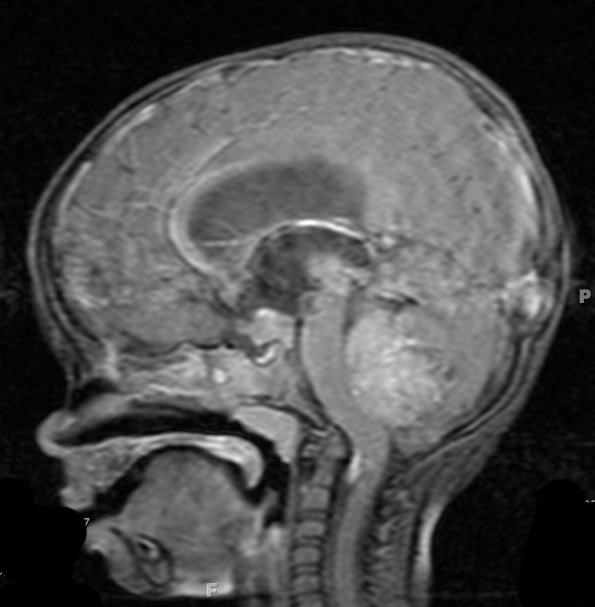

Case 4 History ---- [2yo female who presented with frequent vomiting with weight loss and ataxia. MRI showed a large posterior fossa mass centered in the fourth ventricle with severe hydrocephalus]. ---- 4A This sagittal T1-weighted contrast administered scan shows patchy enhancement.